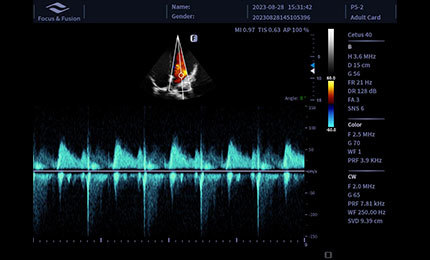

CW

Stosowane do pomiaru wysokoprzepływowego przepływu krwi wewnątrz serca, wykazuje oczywiste zalety w ilościowej analizie zwężenia i niedomykalności.